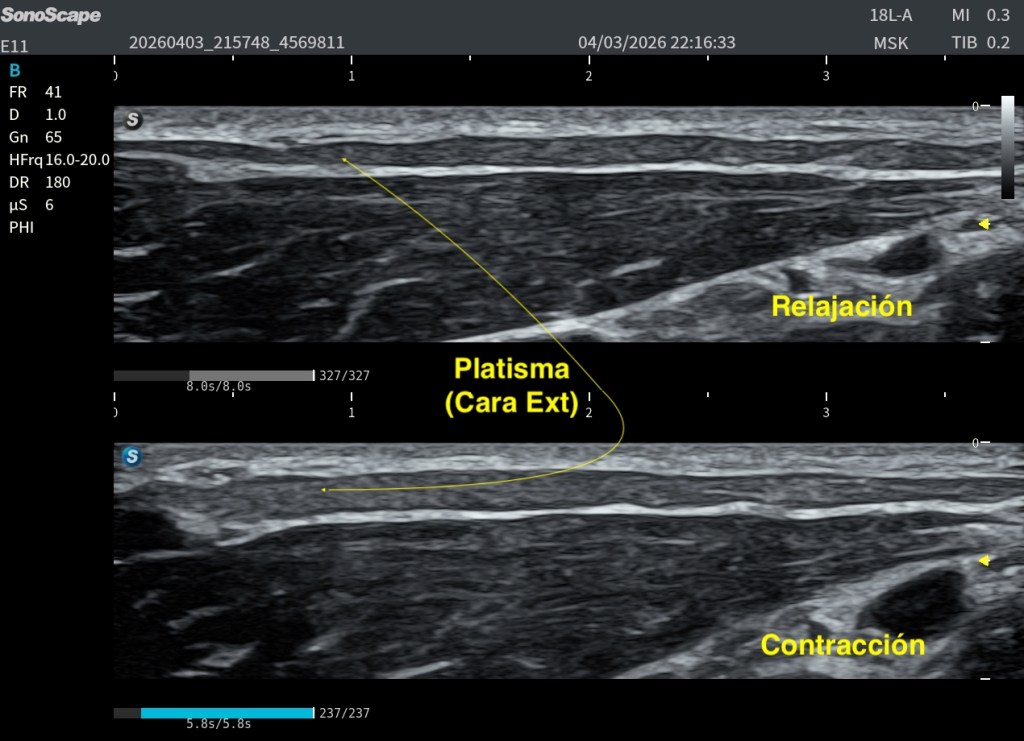

Un aspecto especialmente útil para su reconocimiento es su comportamiento dinámico. En el caso que da soporte a este post, al solicitar la contracción al paciente, se observa que las fibras laterales tienden a engrosarse, mientras que las fibras mediales se aplanan.

La alteración más habitual no es su ausencia, sino su cambio estructural con la edad. Las conocidas bandas platismales representan la manifestación clínica más frecuente. Estudios ecográficos han demostrado que estas bandas corresponden a un comportamiento dinámico real del músculo: durante la contracción, el grosor del platisma aumenta significativamente dentro de la banda (≈37,9%), mientras que en las zonas adyacentes puede incluso disminuir (≈20,3%) (Van der Lei et al., 2023). Esto refuerza la idea de que no se trata solo de un fenómeno estético, sino de una reorganización funcional del músculo y su interacción con la piel y la fascia.